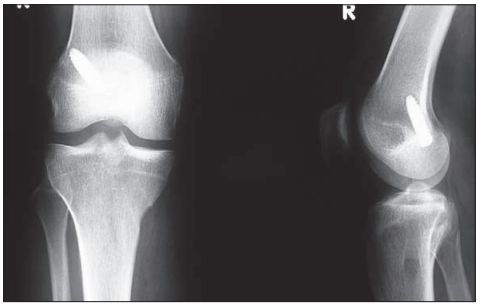

Migracja śruby piszczelowej poza kanał kostny

/ 2Zdjęcie RTG

Stan po usunięciu śruby